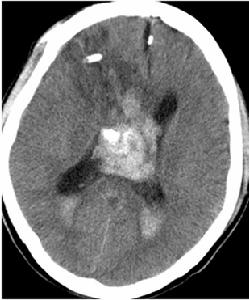

CT掃描見腫瘤位於一側腦室內或位於透明膈在腦室內邊界清楚呈圓形等密度或略高而不均勻密度影半數以上腫瘤有點狀鈣化,當鈣化灶較大時X線平片也可見到。幕上中樞神經細胞瘤增強後腫瘤有中度至明顯強化MRI成像優於CT,對腫瘤範圍及所處部位有診斷價值可見多數腫瘤與透明隔或側腦室壁有關。腫瘤實質部分T1W為等或稍高信號,T2W為高信號,瘤內可見血管流空影。部分腫瘤常伴有出血靜脈注入順磁性顯影劑後,可見輕度增強腫瘤與側腦室壁或透明膈相附著(圖1)。